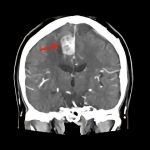

断層撮影